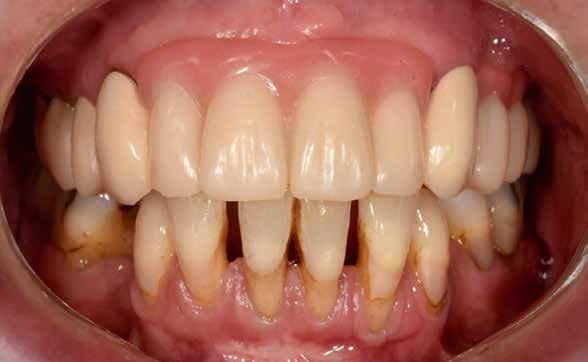

Interdiszciplináris fogászati kezelés myofunkcionális készülék, alignerek és protetikai ellátás alkalmazásával

MED. DENT Abradált frontfogakkal rendelkező felnőtt páciens interdiszciplináris kezelése